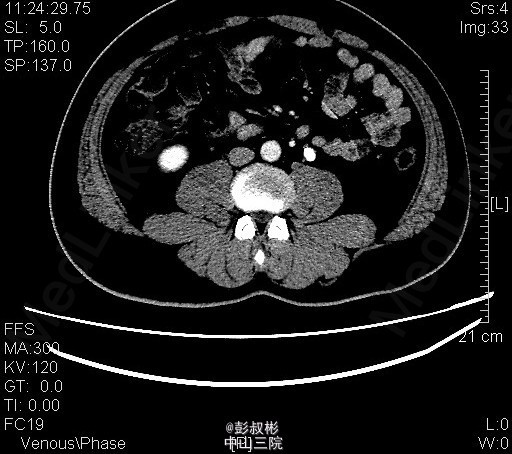

1、体检发现左输尿管结石2月 2、患者2月前体检发现左输尿管结石,无腰痛,无其他部位反射痛,无发热,无恶心,当时未给予治疗。今为求进一步治疗来我科住院,起病以来患者一般情况尚可,体重无下降。

3、查体:双肾区无红肿、隆起,左肾区叩击痛(-),右肾区叩击痛(-),左侧肋脊点、肋腰点压痛(-),右侧肋脊点、肋腰点压痛(-)。腹平软,左侧输尿管走行区压痛(-),右侧输尿管走行区压痛(-),膀胱区无膨隆,压痛阴性 4、辅助检查: 我院 腹部平片 左输尿管上段结石 ;泌尿系b超 前列腺增大;右肾多发结石;左肾形态失常;左输尿管上段结石并左肾积液。CT示左输尿管上段结石、左肾小结石

5、诊断:左输尿管上段结石并左肾积液 6、入院后予以完善术前检查,未见明显手术禁忌,在全麻下行“单孔腹腔镜下左输尿管切开取石术”,术后予以一级护理,心电监护,低流量吸氧,营养支持,抗炎对症治疗。术后注意观察事项:保持引流管及尿管通畅,留意尿量及引流量